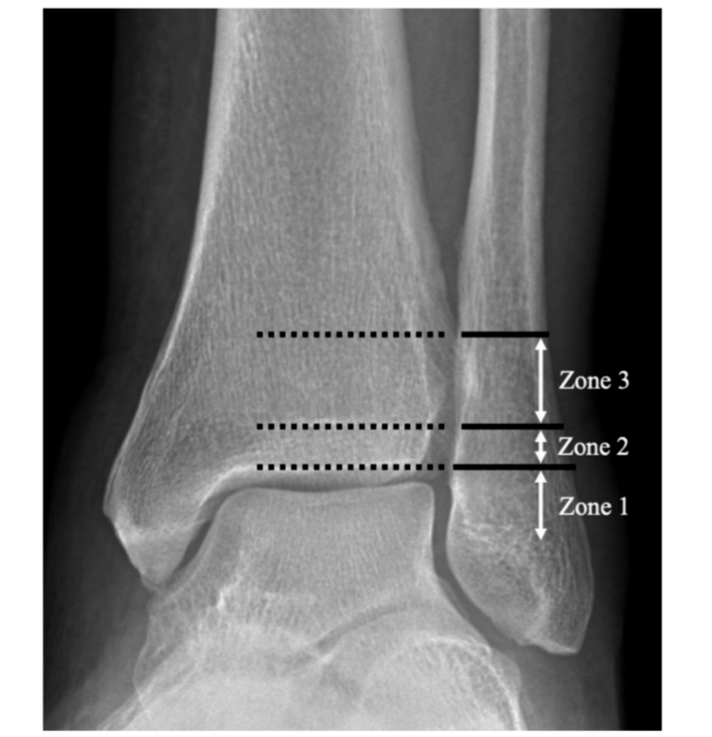

图2Danis-Weber B型骨折,根据近端骨折块最远端位置分区。1区定义为骨折块最远端位于胫骨远端关节面平面以下;2区为位于胫骨远端骺线闭合瘢痕与远端关节面之间;3区为骺线闭合瘢痕以上。

图3 分区示意图。